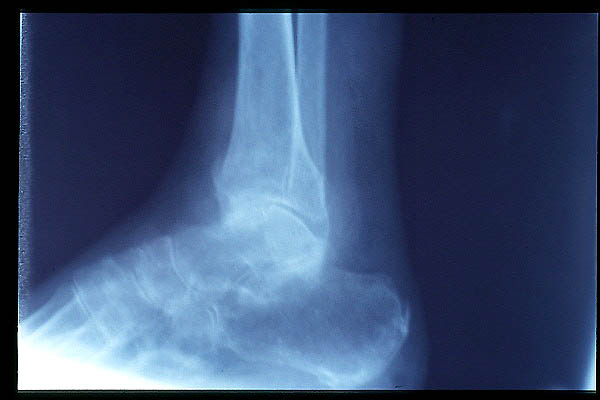

APR Fractura bimaleolar de tobillo

APR Fractura de peroné

APR Fractura tibial